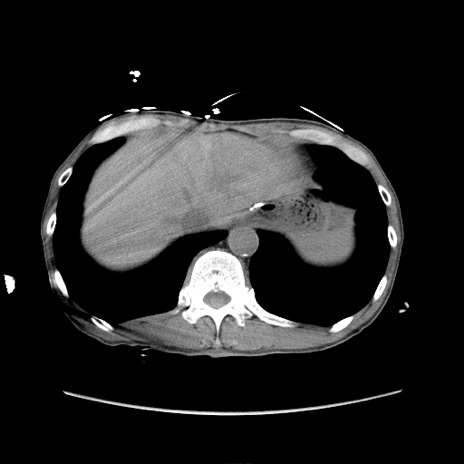

冠状断像

【症例】 60歳代男性

【主訴】 下腹部痛

【現病歴】 本日夜中より下腹部痛の症状認め、受診。

【既往歴】 膀胱癌(膀胱全摘+尿管皮膚瘻術) 、胃癌術後

【身体所見】 BT 35.3℃、PR 58/min、BP 136/98mHg、腹部平坦、軟、腸蠕動音±、ストマ留置あり、左上腹部~正中部に圧痛あり、反跳痛なし。

【データ】WBC 5100、CRP0.01